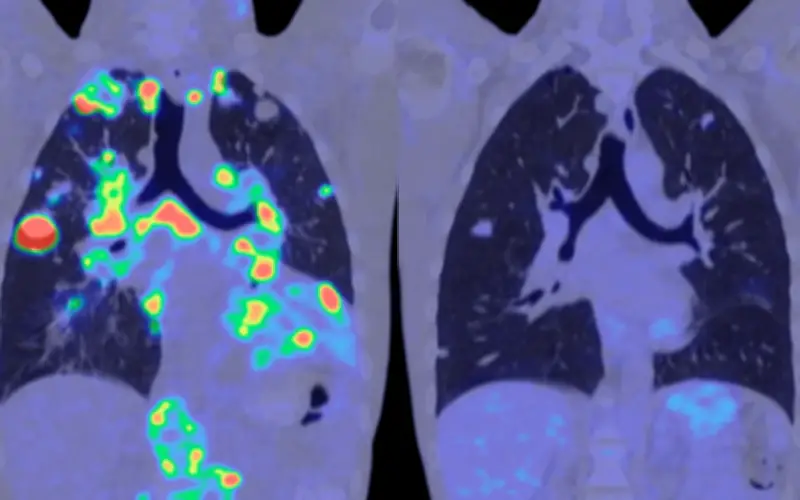

Mediante la aplicación de algoritmos de aprendizaje automático para analizar los complejos datos de metilación, los resultados fueron extraordinariamente alentadores:

- La prueba alcanzó una especificidad del 98%, lo que significa muy pocos falsos positivos

- Detectó aproximadamente el 63% de todos los cánceres en todas las etapas

- Identificó alrededor del 55% de los cánceres en fase inicial

- En vigilancia de cáncer de hígado en personas de alto riesgo, detectó casi el 80% de los casos con especificidad superior al 90%

Más allá de la simple detección del cáncer, MethylScan demostró capacidad para identificar el tejido de origen de las señales cancerosas. Los patrones de metilación permitieron determinar qué órganos específicos estaban experimentando estrés o daño, incluso sin conocimiento previo de la enfermedad.

Los autores describen esta capacidad como un "radar de salud para el cuerpo" que podría revolucionar el monitoreo médico preventivo. "Es un avance emocionante que nos acerca al sueño de lograr un único análisis de sangre para la detección universal de enfermedades", concluyen los investigadores.